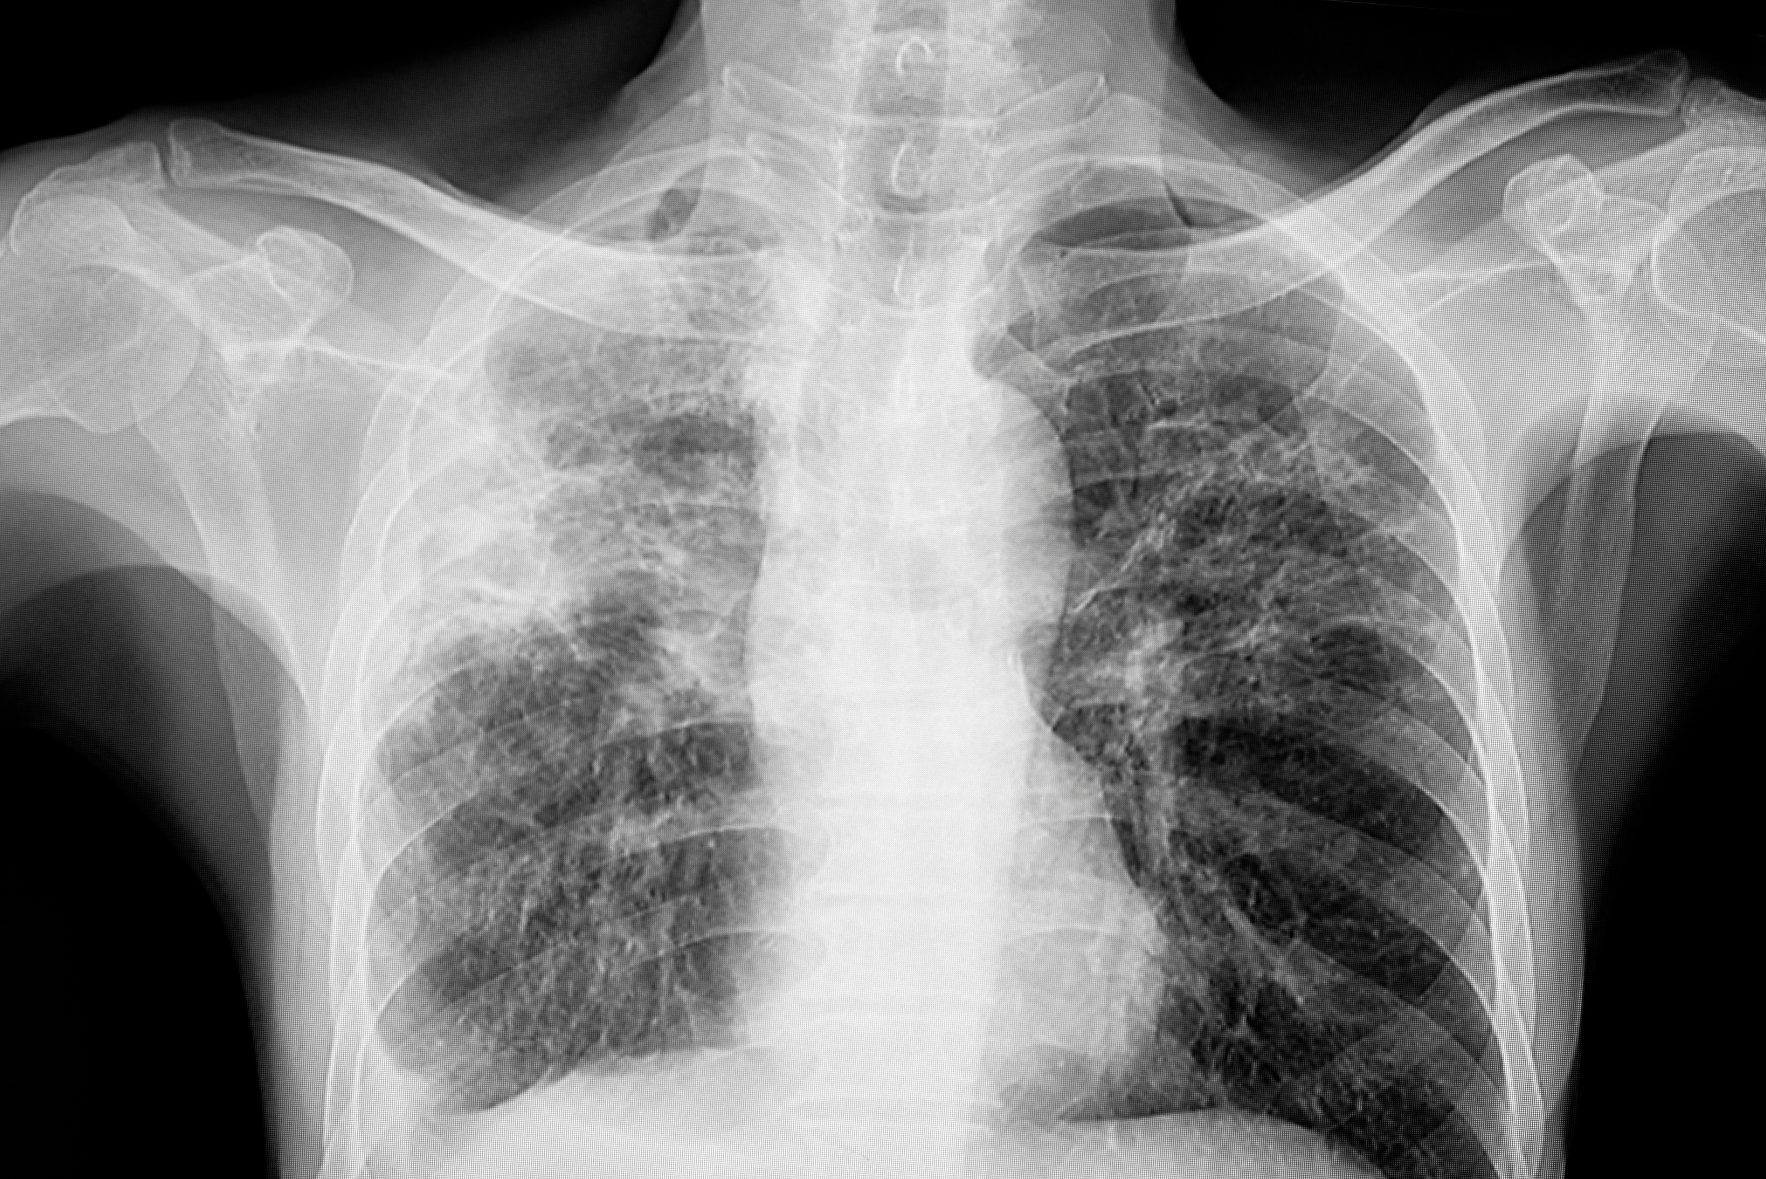

Dr Lo emphasised that one of the earliest and most common signs of active pulmonary TB is a persistent cough lasting more than two weeks.

Other symptoms include night sweats, low-grade fever, fatigue, unintentional weight loss, and in more advanced cases, coughing up blood-stained sputum or chest pain.